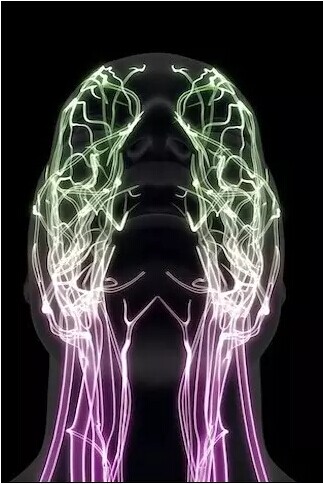

面部神经

下体神经分布

颈椎、大脑